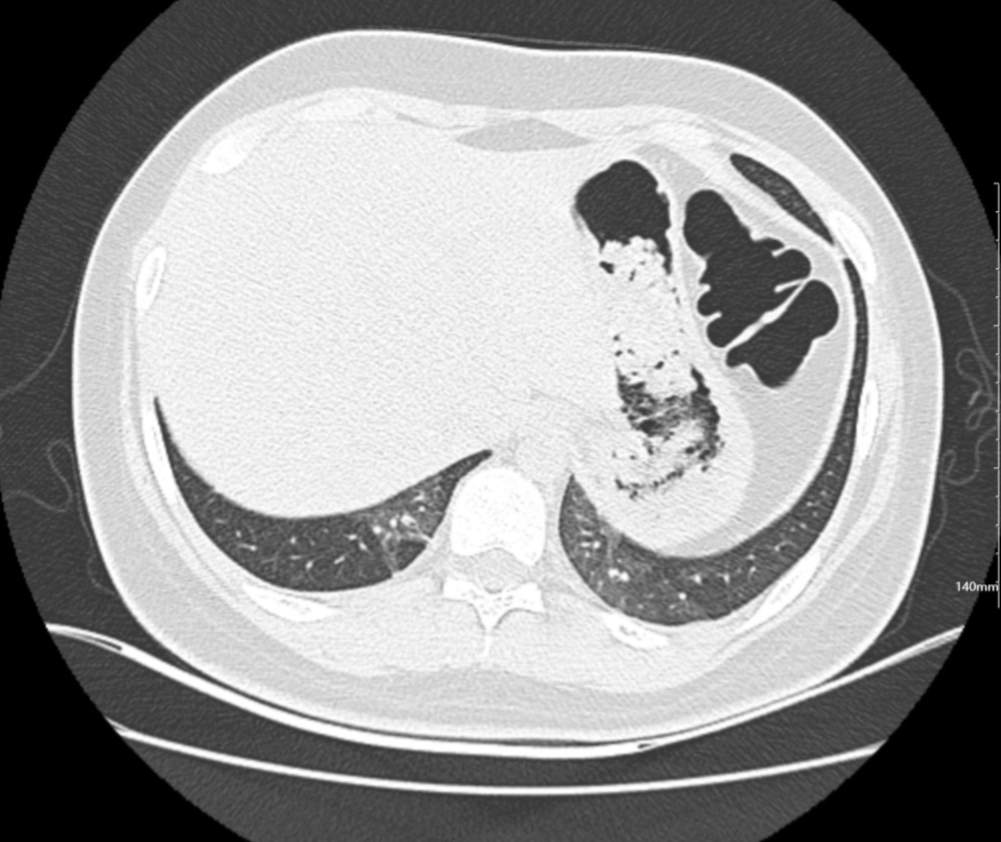

肺部CT:

百日咳肺炎CT 表现

支气管血管束增粗且伴 < 2 个肺叶的磨玻璃密度影, 多提示为单纯性百日咳肺炎。(下图:支气管血管束增粗, 两肺下叶基底段少许磨玻璃密度影)

如出现肺内支气管血管束增粗, 伴≥3 个肺叶斑片影、亚段性实变及支气管气象时, 提示患儿病情较重,可能合并其他感染。